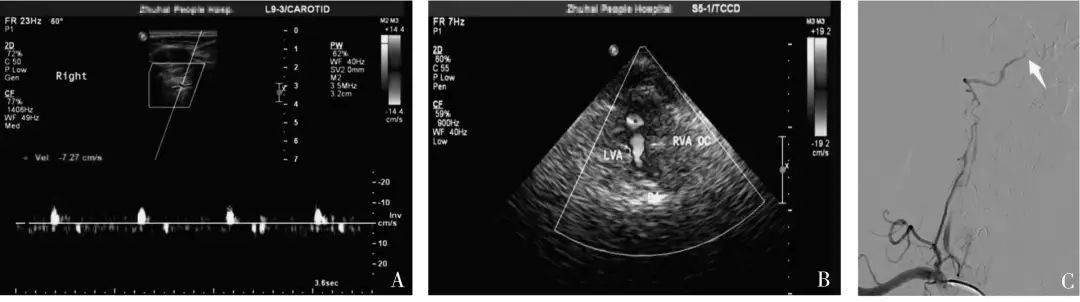

2019年9月,暨南大学附属珠海医院报道了一项研究[1],经由CTA或DSA结果证实为单侧椎动脉颅内段闭塞患者40 例,由未规范培训组医师和规范培训组医师分别进行血管超声检查,将两组超声诊断结果与金标准结果进行比较,并对两组不同资历医师进行诊断一致性分析。

结果:规范培训组诊断椎动脉颅内段闭塞的敏感度及符合率(均为95%)明显高于未规范培训组(均为75%),不同资历的超声医师对于椎动脉颅内段闭塞的一致性检验结果Kappa 值为0.273,诊断一致性较差。

中国脑卒中血管超声检查指导规范[2]指出:若椎动脉闭塞于小脑后下动脉分支之前,椎动脉颅外段可探及低速单峰型(无舒张期血流信号);若椎动脉闭塞于小脑后下动脉之后,椎动脉颅外段可探及低速高阻型(舒张期流速低平)血流信号。

本研究中,未规范培训组椎动脉椎间隙段频谱形态呈“高阻型”10 例中,全部诊断为椎动脉发育不良,“单峰型”30 例全部诊断为颅内段闭塞。

当椎动脉椎间隙段内径≤2.5 mm,频谱形态呈低速高阻型改变时,既有可能是椎动脉发育不良,也有可能是椎动脉颅内段闭塞,此时应联合TCCS(或TCD) 检查,直观地从枕窗观察双侧椎动脉颅内段的血流充盈情况。